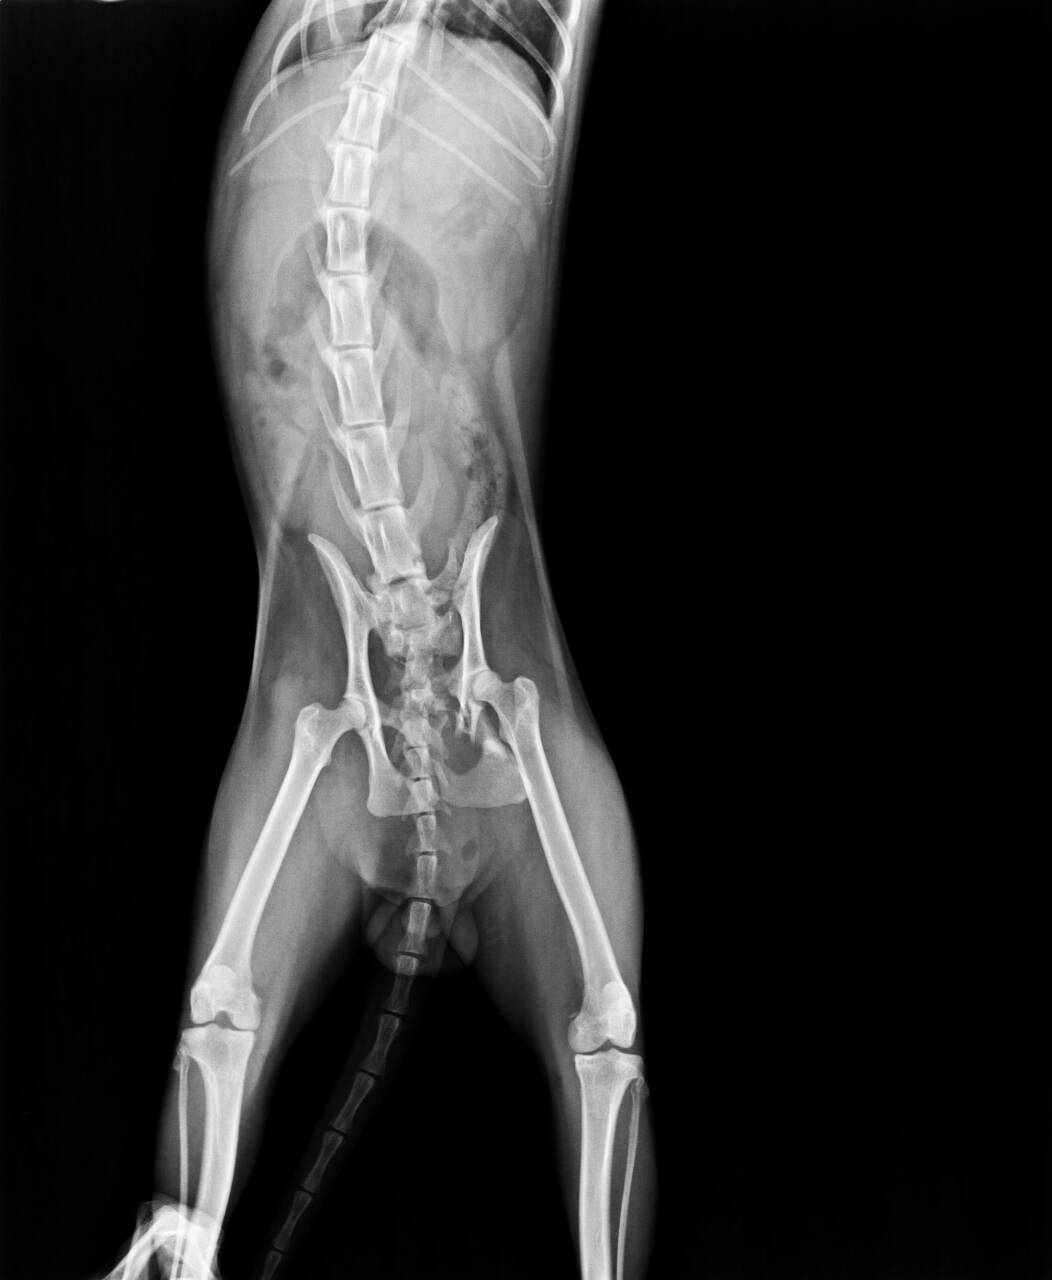

由同事幫忙送醫後,醫生表示外傷主要為下顎斷裂無法進食,無骨折,頭部進入空氣,有吐血,身體激素因求生反應,部分指數標高或偏低,疑似為車禍所致。

血檢及X光之後會再補上。動物近況說明: 12/3(四)

女護士去摸摸他發現都趴著沒有站起來,所以重新照X光檢查下半身,

發現骨盆也有受傷,在支撐點破裂(脫臼)了,整個上移了一個脊髓,所以雙腳雖然有反應但是無法撐起整個身體,這部份也需要手術治療。